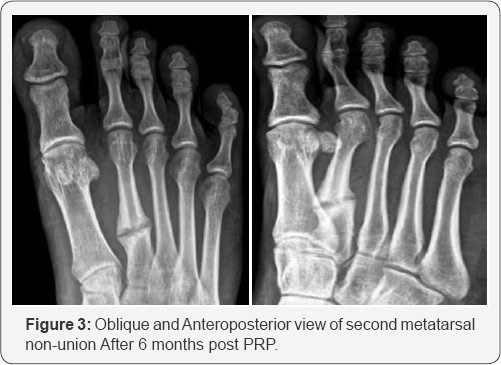

Evaluation of fracture healing was confirmed by clinically and radiologically, serial radiological views were taken at every 4 weeks interval by two planes, healing of nonunion bone confirmed radiologically by bridging callus formation and crossing of bone trabeculae network at each follow up visit (Figures 2 & 3). Clinically we confirmed union by absence of pain, improvement in range of motion of affected extremities. Stress testing manually shows absence of motion at fracture site. We followed patient up to 6 months.